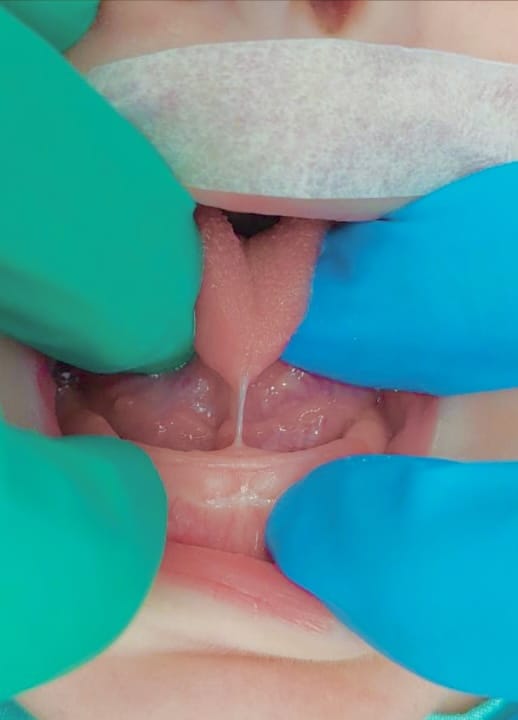

ANQUILOGLOSIA: Cuando el tratamiento es más que un simple corte

El frenillo lingual corto, o anquiloglosia, puede dificultar que un bebé se alimente bien del pecho. Este artículo, basado en más de 25 años de práctica clínica, explica la importancia de evaluar adecuadamente el tipo de frenillo. Se describe cómo una cirugía realizada bajo sueño profundo controlado (sedación profunda) por un equipo especializado puede ser la solución más efectiva y segura, restaurando la función normal de la lengua.

Muchos bebés y sus madres enfrentan desafíos al inicio de la lactancia. Una causa frecuente, aunque no siempre identificada por el equipo médico, es un frenillo bajo la lengua, demasiado corto o tenso. Esto impide que el bebé mueva su lengua libremente para prenderse y succionar correctamente, lo que provoca dolor en la madre, poca transferencia de leche y mucho estrés para ambos. La clave está en saber no solo si el frenillo está corto, sino también cómo es su estructura, para elegir el mejor camino a seguir.

Entender el Frenillo para Elegir el Tratamiento Correcto

No todos los frenillos son iguales. Al evaluar a un bebé, es esencial palpar para sentir y observar su frenillo con detalle. Algunos son finos, como una telita flexible, y responden bien a un pequeño corte sencillo realizado en consultorio. Sin embargo, otros son gruesos, firmes y contienen fibras que son como pequeñas cuerdas tensas que tiran de la lengua hacia abajo. Estos últimos son los que verdaderamente limitan el movimiento y suelen no mejorar con intervenciones superficiales o cortes sencillos.

He visto a lo largo de mi carrera, y en casos como el de un bebé que requirió tres intentos diferentes, que cuando estas fibras profundas no se liberan por completo, el problema persiste. El bebé continúa con dificultades para alimentarse, la madre sigue con molestias y pueden aparecer compensaciones como tensiones en el cuello y la espalda del niño. Esto lleva a un ciclo de frustración y visitas a múltiples especialistas sin una solución definitiva.

Para estos casos complejos, la opción más efectiva es una pequeña cirugía llamada frenuloplastía, realizada mientras el bebé está en un sueño profundo y seguro (sedación profunda) administrada por un médico anestesiólogo pediátrico en un ambiente hospitalario. Este entorno permite trabajar con total precisión: liberar todas esas fibras tensas profundas, recolocar el tejido para que cicatrice de manera amplia y así restaurar por completo el movimiento que la lengua necesita para mamar. Es un procedi miento breve, pero la diferencia en los resultados es abismal comparada con intentar lo mismo con el bebé despierto.

Conclusión y Mensaje para las Familias

La decisión de realizar una intervención bajo sedación no se toma a la ligera. Se reserva para los casos difíciles donde otras medidas no han funcionado. Su gran valor es que ofrece una solución definitiva, interrumpiendo un camino de dificultades. Aunque, lamentablemente, a veces se llega a esta solución después de que la lactancia ya se ha visto muy afectada, corregir el problema sienta las bases para una alimentación complementaria futura exitosa y un desarrollo oral saludable. Como profesional, mi compromiso es evaluar con experiencia y honestidad, explicando a las familias todas las opciones. El mejor resultado siempre se logra con un enfoque en equipo, que puede incluir apoyo de asesora de lactancia, fisioterapeuta oral, otorrinolaringólogo, pediatra y otros especialistas, para guiar al bebé hacia una recuperación completa. Este enfoque se basa en protocolos clínicos y estudios publicados en revistas especializadas de pediatría, odontología y otorrinolaringología, que respaldan la evaluación funcional y el tratamiento quirúrgico completo para la anquiloglosia restrictiva. La seguridad del bebé es siempre nuestra máxima prioridad en este proceso.